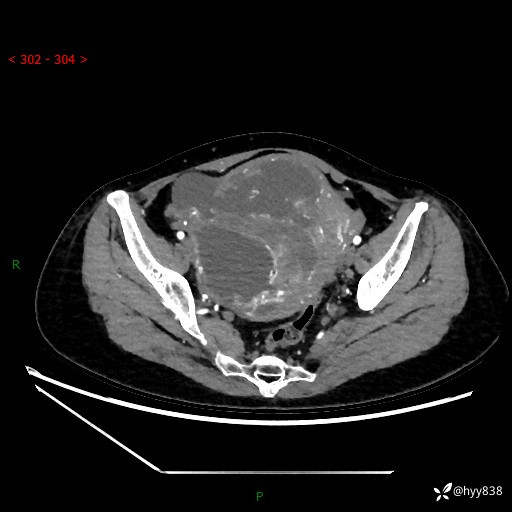

辅助检查:CT

增强(动脉期+静脉期)